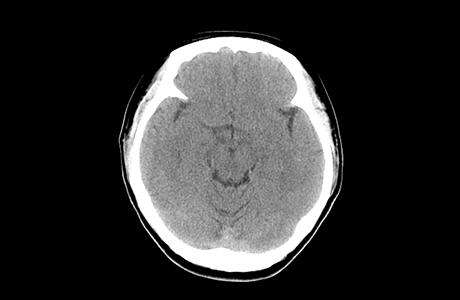

• 뇌 컴퓨터 단층 촬영술 (CT)

CT는 검사 시간이 짧으며 안전합니다. 급성기 뇌졸중 초기 치료를 결정하기 위해 가장 먼저 시행되는 검사입니다. 뇌경색의 경우 저음영으로 나타나고, 뇌출혈인 경우 고음영으로 나타납니다.